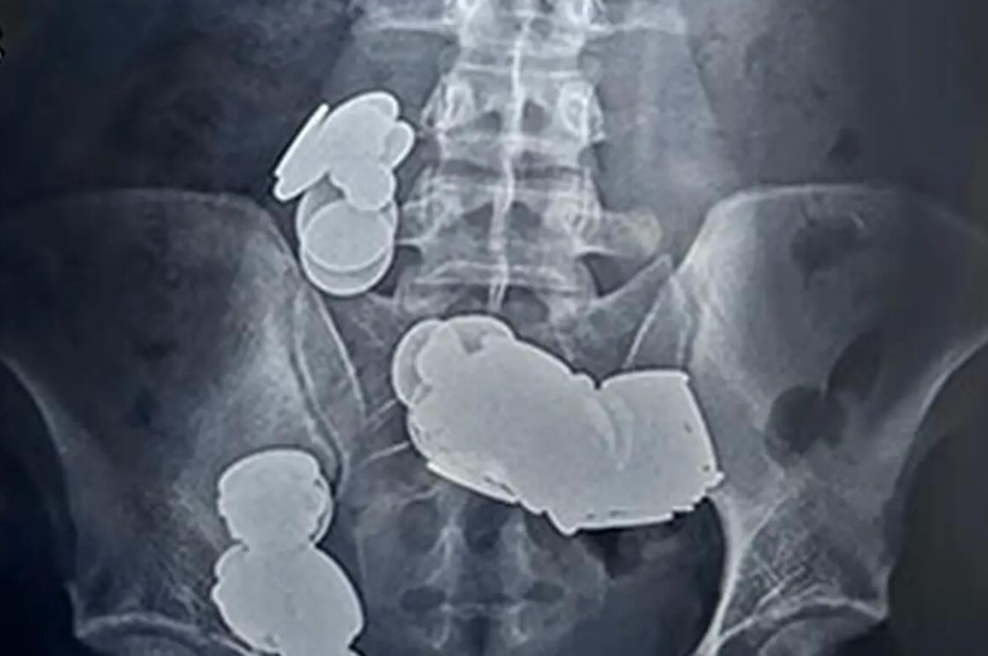

Toda posledice so bile katastrofalne. Mladi Indijec je dobil hude bolečine v trebuhu, večkrat je tudi bruhal. Zaradi tega je pomoč poiskal v bolnišnici, kjer so ga slikali z rentgenom, poroča oe24. Kar so zdravniki videli na slikah, jih je osupnilo.

Kovanci so se zaradi magnetne sile sprijeli skupaj, kar je vodilo v črevesno obstrukcijo. A 26-letnik je imel neizmerno srečo, saj je kirurgom uspelo odstraniti vse kovance in magnete, pacient pa je po enem tednu lahko zapustil bolnišnico.